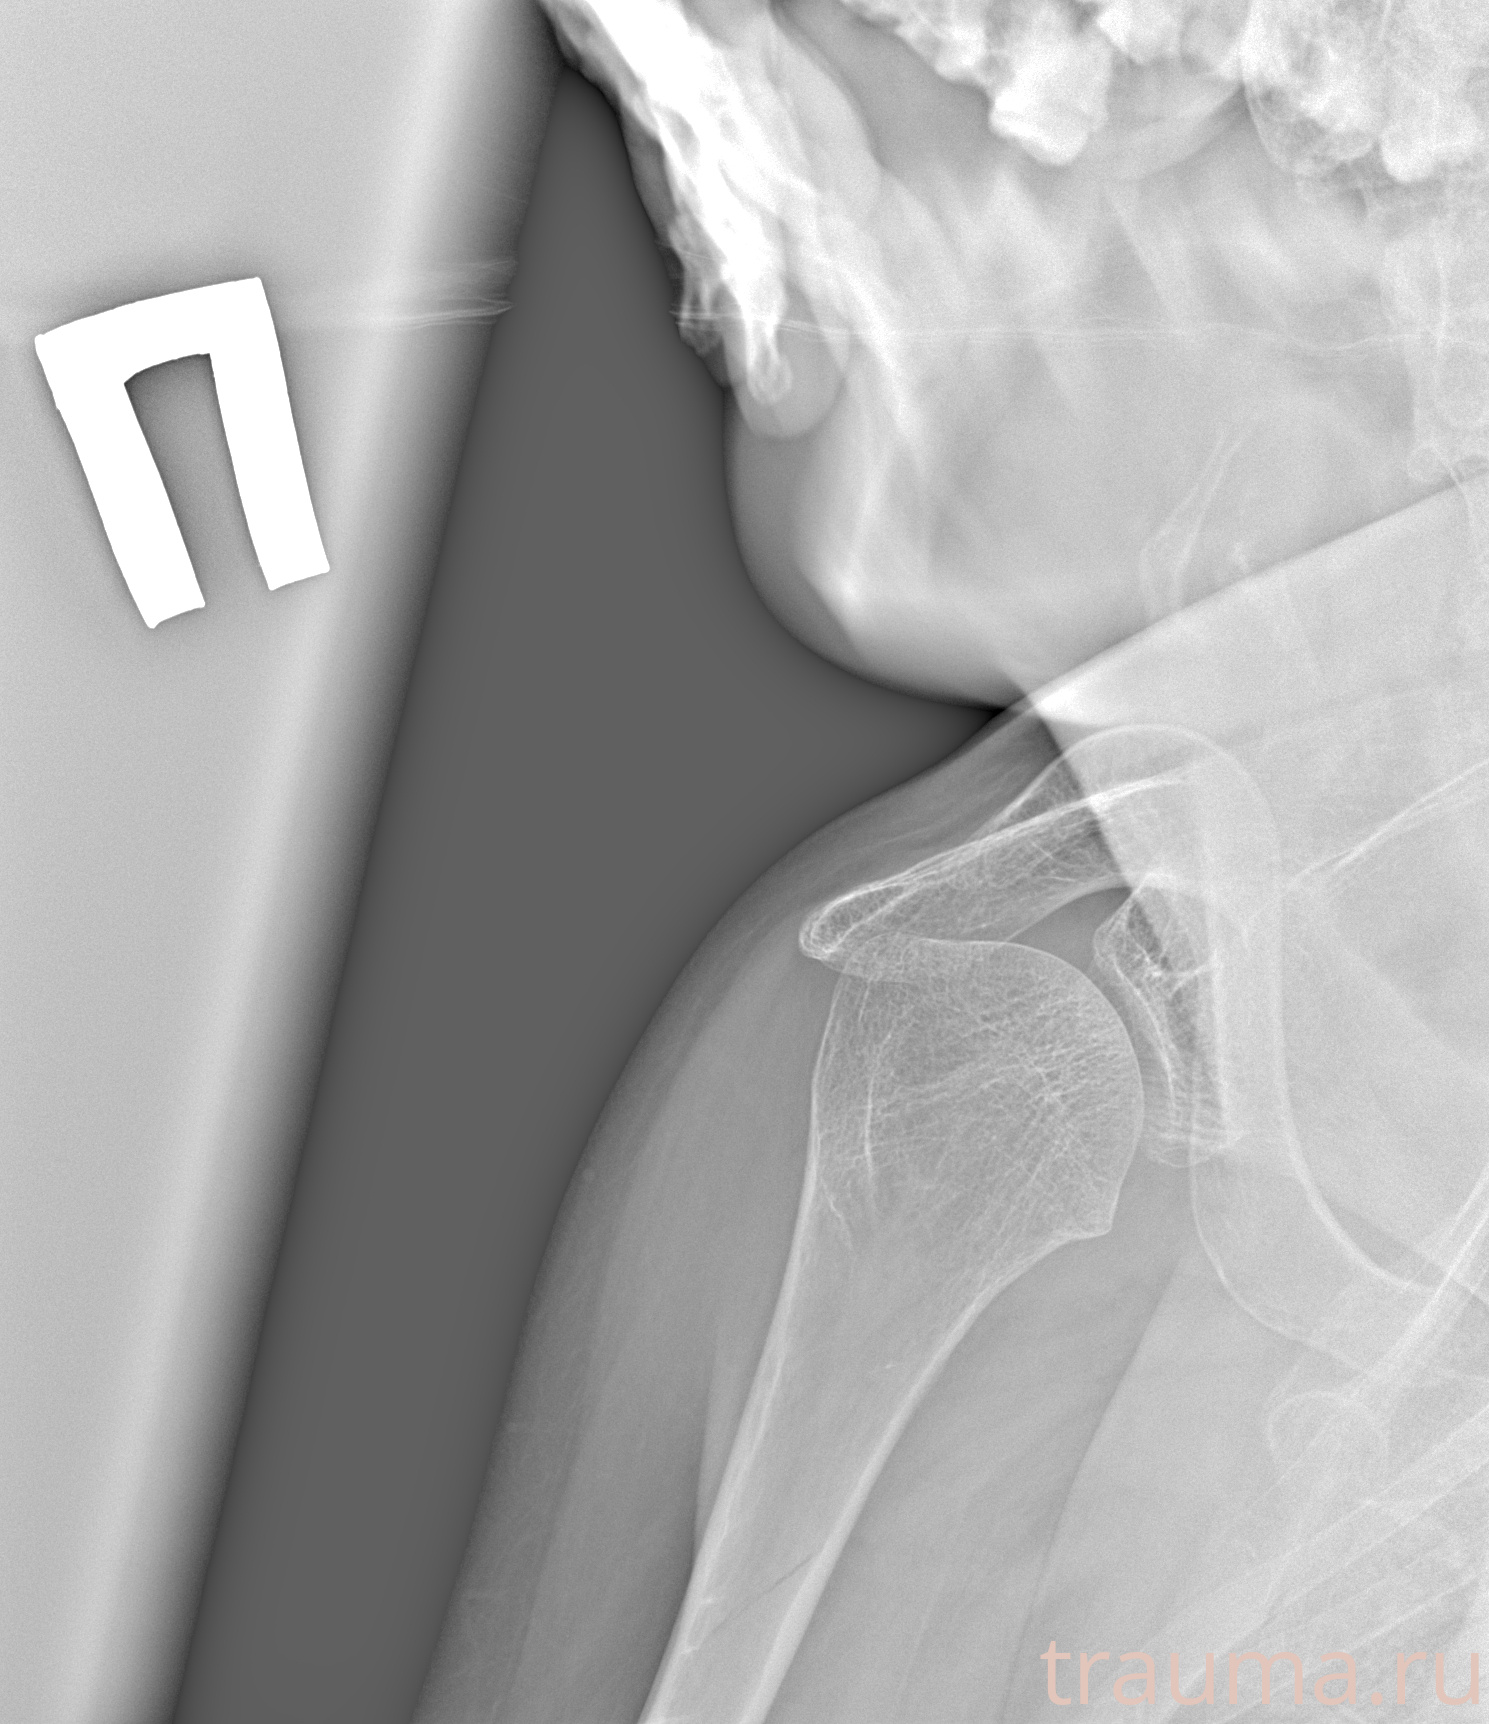

Рентгенограммы

Рентген на дому: по вашему адресу приезжает врач-рентгенолог, травматолог-ортопед с мобильным рентгеновским аппаратом, проводит диагностику травмы или заболевания, делает необходимые рентгенограммы, дает рекомендации по дальнейшему лечению. Получить качественные снимки в домашних условиях возможно благодаря уникальной методике, разработанной МосРентген Центром для института  Склифосовского

при переломе шейки бедра и пневмонии от компании МосРентген Центр - партнера Института имени Склифосовского